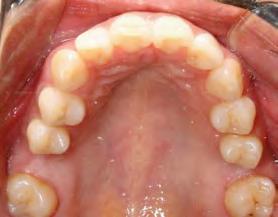

52 | SONRIENDO AL FUTURO

Tratamiento ortodóncico en paciente adulto tratado con extracciones de primeros molares permanentes. Reporte de caso

en paciente adulto tratado con extracciones de primeros molares permanentes. Reporte de caso

Dentista y Paciente 52 Sonriendo al futuro